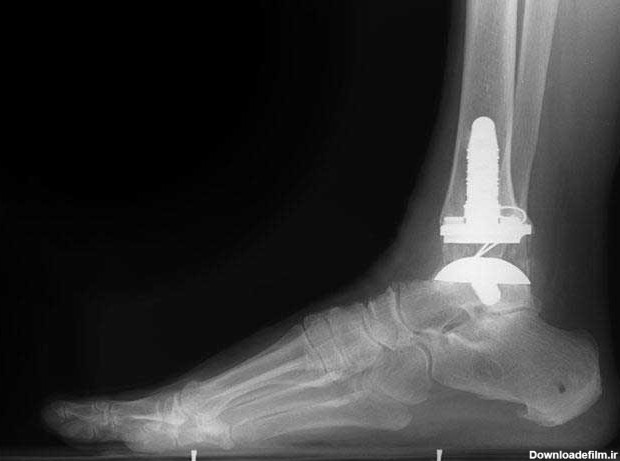

سالم خبر : مدیر کانون هموفیلی آذربایجانamp;zwnj;شرقی گفت: نخستین عمل فیکس مچ پا بر روی بیمار هموفیلی ...